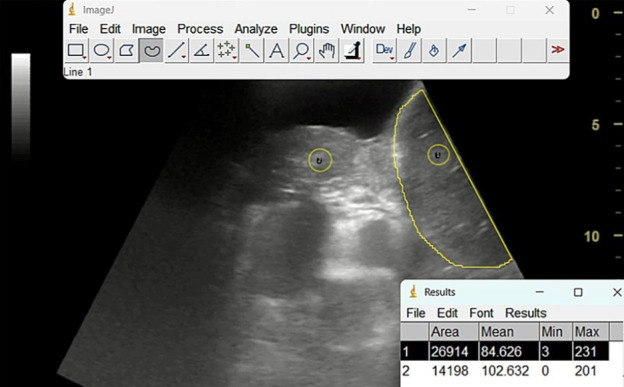

Malignant pleural effusion (MPE) affects up to 15% of cancer patients, with nearly 30% of symptomatic cases developing non-expandable lung (NEL), a condition characterised by the lung's failure to fully re-expand post-drainage, thereby impeding proper pleural apposition and leading to several adverse outcomes. Inadequate diagnostic certainty leads to prolonged hospitalisation, repeated invasive procedures, drainage complications, high pleurodesis failure rates, increased healthcare costs and diminished patient quality of life. Conventional diagnostic methods, predominantly based on post-procedural chest radiography and computed tomography, frequently delay accurate diagnosis, underscoring the need for noninvasive pre-procedural techniques. Emerging evidence supports thoracic ultrasound, particularly the application of M-mode during breath-hold, as a promising modality for early NEL detection by identifying the absent sinusoidal sign and reduced lung movement. Experimental approaches, including speckle tracking imaging, two-dimensional shear wave elastography and quantitative ultrasound assessments via the lung/liver echogenicity ratio, also show potential, albeit with limitations that warrant further validation. Integration of artificial intelligence into multimodal imaging workflows may enhance diagnostic precision and predictive modelling, ultimately facilitating personalised therapeutic strategies and transforming the management of NEL in MPE. These innovations promise to reduce invasive diagnostics and healthcare costs while improving patient outcomes and quality of life in MPE-associated NEL.